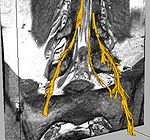

Segmentation of Nerve and Nerve Ganglia in the SpineAutomatic segmentation of neural tracts in the dural sac and outside of the spinal canal is important for diagnosis and surgical planning. The variability in intensity, contrast, shape and direction of nerves in high resolution MR images makes segmentation a challenging task. More...

Fiber Tract Modeling, Clustering, and Quantitative AnalysisThe goal of this work is to model the shape of the fiber bundles and use this model description in clustering and statistical analysis of fiber tracts. More... |

Joint Registration and Segmentation of DWI Fiber TractographyThe goal of this work is to jointly register and cluster DWI fiber tracts obtained from a group of subjects. More... |

DTI Fiber Clustering and Fiber-Based AnalysisThe goal of this project is to provide structural description of the white matter architecture as a partition into coherent fiber bundles and clusters, and to use these bundles for quantitative measurement. More... |